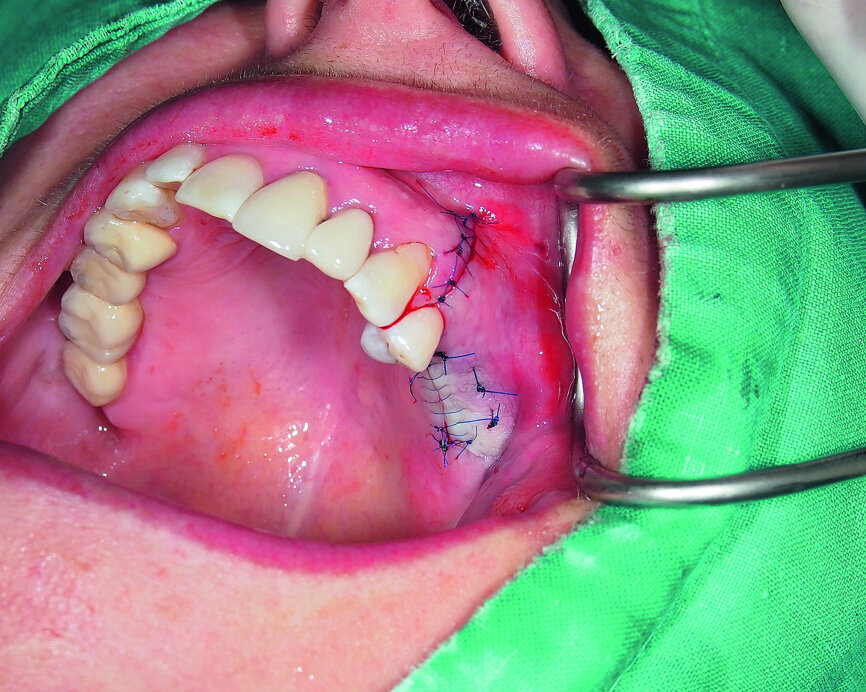

Fig. 20: Wound closure with monofilament sutures.

The bone void was filled with a xenogeneic bone graft and covered with an absorbable collagenous membrane (Fig. 19). Closure was obtained by the use of a PVDF monofilament suture (RESOPREN 6/0; Fig. 20). Healing was uneventful and the final prosthodontic restoration was a premolar and molar splinted together for a more beneficial load transfer to the surrounding bone.